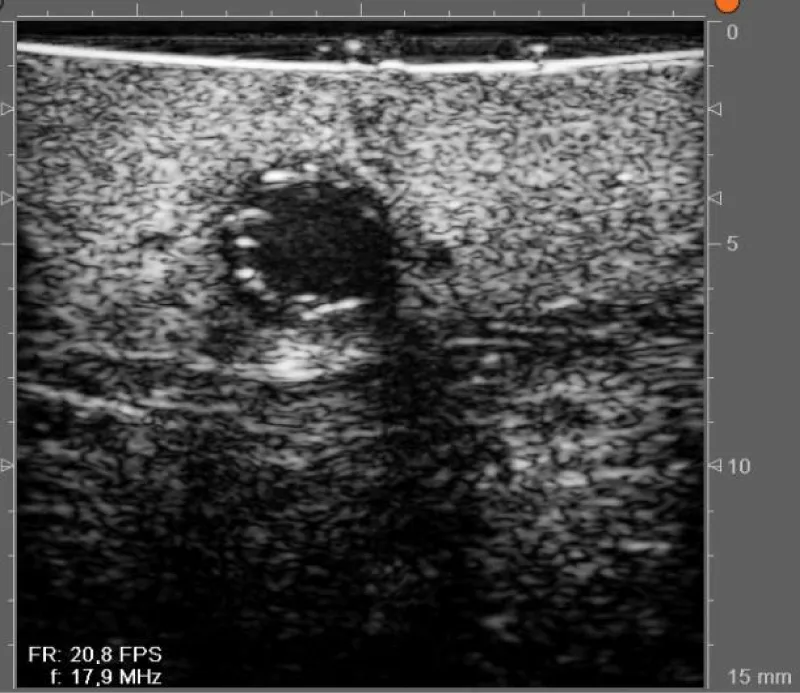

In case of doubt about the quality of the anastomosis (due to technical challenges during the realization of the anastomosis, or obtainment of nonideal PI values), we can assess the result of the anastomosis with the epicardic echography (Figures 12,13):

Figure 13: Doppler echographic evaluation of an anastomosis between the left internal mammary artery and the left anterior descending artery.